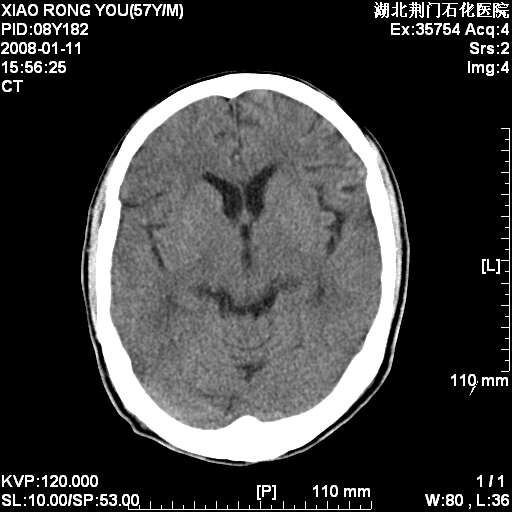

3天后增强

增强明显强化,转移?

如此血管样强化表现,转移瘤不好解释,考虑脑膜瘤或血管瘤

平扫无明显占位及水肿、增强扫描强化明显以血管瘤可能性大